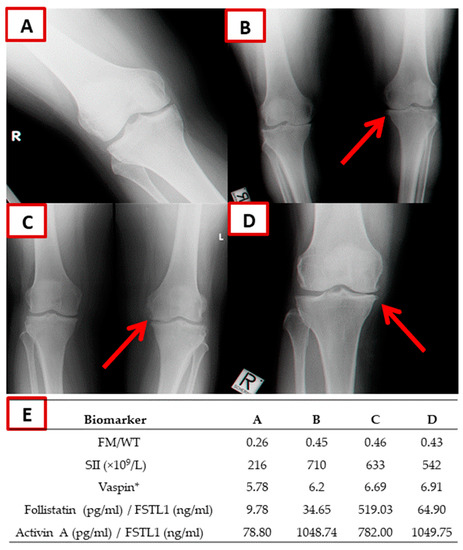

| Covariate | Control (N = 519) | KOA (N = 98) | p | p * |

|---|---|---|---|---|

| Age (years) | 51.90 ± 0.38 | 56.16 ± 1.08 | 0.00002 | |

| WHR | 0.93 ± 0.003 | 0.94 ± 0.009 | NS | NS |

| BMI (kg/m2) | 29.62 ± 0.21 | 32.38 ± 0.51 | 0.000001 | 0.0003 |

| FM/WT | 0.32 ± 0.003 | 0.38 ± 0.008 | 3.63 × 10−7 | 0.0007 |

| SMM/WT | 0.31 ± 0.002 | 0.27 ± 0.005 | 0.000004 | 0.03 |

| hs-CRP (mg/L) | 1.50 ± 0.24 | 3.66 ± 0.84 | 0.001 | 0.001 |

| SII (×109/L) | 455.01 ± 13.81 | 615.22 ± 40.96 | 0.000004 | 0.00002 |

| Vaspin ** | 5.96 ± 0.04 | 6.44 ± 0.16 | 0.0003 | 0.001 |

| Follistatin ** | 6.13 ± 0.03 | 6.39 ± 0.07 | 0.004 | 0.009 |

| Activin A ** | 6.51 ± 0.05 | 6.84 ± 0.12 | 0.01 | 0.009 |

| FSTL1 (ng/mL) | 14.00 ± 0.23 | 13.03 ± 0.44 | NS | NS |

| Follistatin (pg/mL)/FSTL1 (ng/mL) | 47.42 ± 1.82 | 69.68 ± 7.71 | 0.00003 | 0.00006 |

| Activin A (pg/mL)/FSTL1 (ng/mL) | 96.10 ± 5.99 | 156.85 ± 21.96 | 0.0002 | 0.0007 |

| KOA Status, Affected (N = 98) vs. Controls (N = 519) | |||

|---|---|---|---|

| Independent Covariate | OR (95% CI) | Β (SE) | p |

| FM/WT | 1.56 (1.20–2.02) | 0.44 (0.13) | 0.0007 |

| SII (×109/L) | 4.03 (2.23–7.27) | 1.39 (0.30) | 0.000003 |

| Vaspin (pg/mL) | 1.39 (1.15–1.68) | 0.33 (0.09) | 0.0005 |

| Follistatin (pg/mL)/FSTL1 (ng/mL) | 1.32 (1.02–1.70) | 0.27 (0.13) | 0.03 |

| Activin A (pg/mL)/FSTL1 (ng/mL) | 1.33 (1.01–1.75) | 0.28 (0.13) | 0.03 |